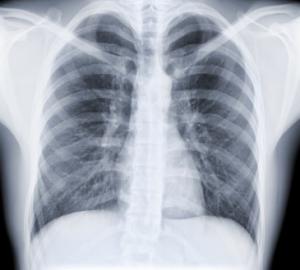

La tuberculosis (TB), que es causada por el Mycobacterium tuberculosis, es una de las enfermedades más mortales en el mundo, según los Centros para el Control y Prevención de Enfermedades (CDC) .

La TB se propaga cuando una persona con una infección activa en los pulmones tose o estornuda gotitas que contienen la bacteria en el aire y se inhala por otra persona.

La enfermedad afecta a los pulmones lo general pero puede afectar a otros órganos. Los síntomas típicos incluyen tos persistente,